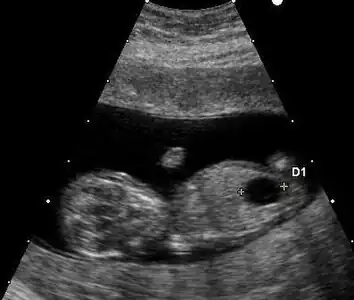

Ultrasound

Prenatal ultrasound can be used to screen for Down syndrome. Findings that indicate increased chances when seen at 14 to 24 weeks of gestation include a small or no nasal bone, large ventricles, nuchal fold thickness, and an abnormal right subclavian artery, among others.[113] The presence or absence of many markers is more accurate.[113] Increased fetal nuchal translucency (NT) indicates an increased possibility of Down syndrome picking up 75–80% of cases and being falsely positive in 6%.[114]

- Ultrasound of fetus with Down syndrome showing a large bladder

Enlarged NT and absent nasal bone in a fetus at 11 weeks with Down syndrome